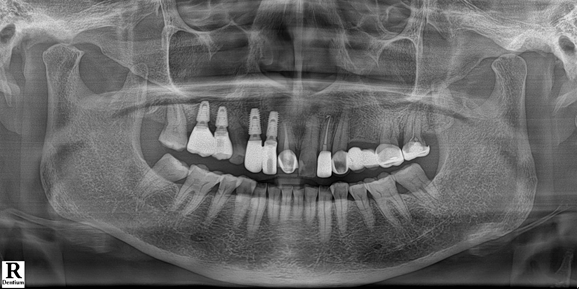

전치부는 지르코니아, 구치부는 보험임플란트 pfm 으로 제작 (70세 여자)

c.c: 앞니가 부러졌고, 오른쪽 어금니가 아파요.